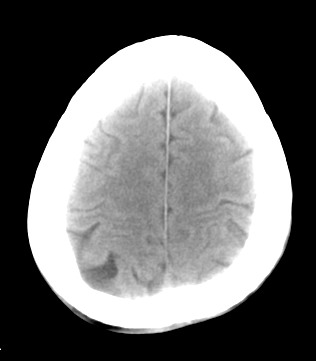

标题: CT17787:头ct,请帮忙看看右顶部有无异常 [打印本页]

男,58岁,偶有头疼

未见明显异常。右顶部低密度影为深入的脑沟。

增宽的脑沟!无异常!

是宽大的脑沟,局部不象有萎缩现象

增宽的脑沟

诊断依据:

低密度影周围脑组织边缘均有一层脑灰质覆盖。

正常啊,是对右顶增宽脑沟有疑问吗